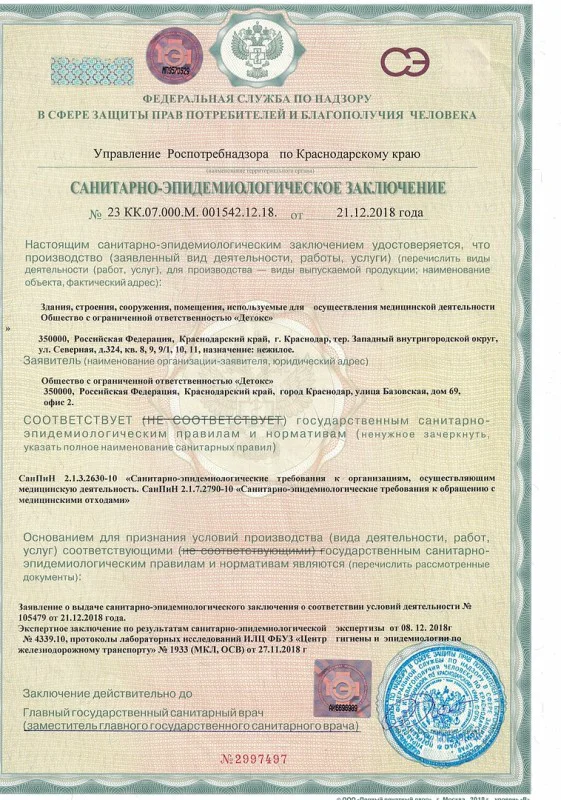

Лицензия на осуществление медицинской деятельности

Лицензия на осуществление медицинской деятельности

Лицензия на осуществление медицинской деятельности

Лицензия на осуществление медицинской деятельности

Лицензия на осуществление медицинской деятельности

Лицензия на осуществление медицинской деятельности

Лицензия на осуществление медицинской деятельности

Лицензия на осуществление медицинской деятельности